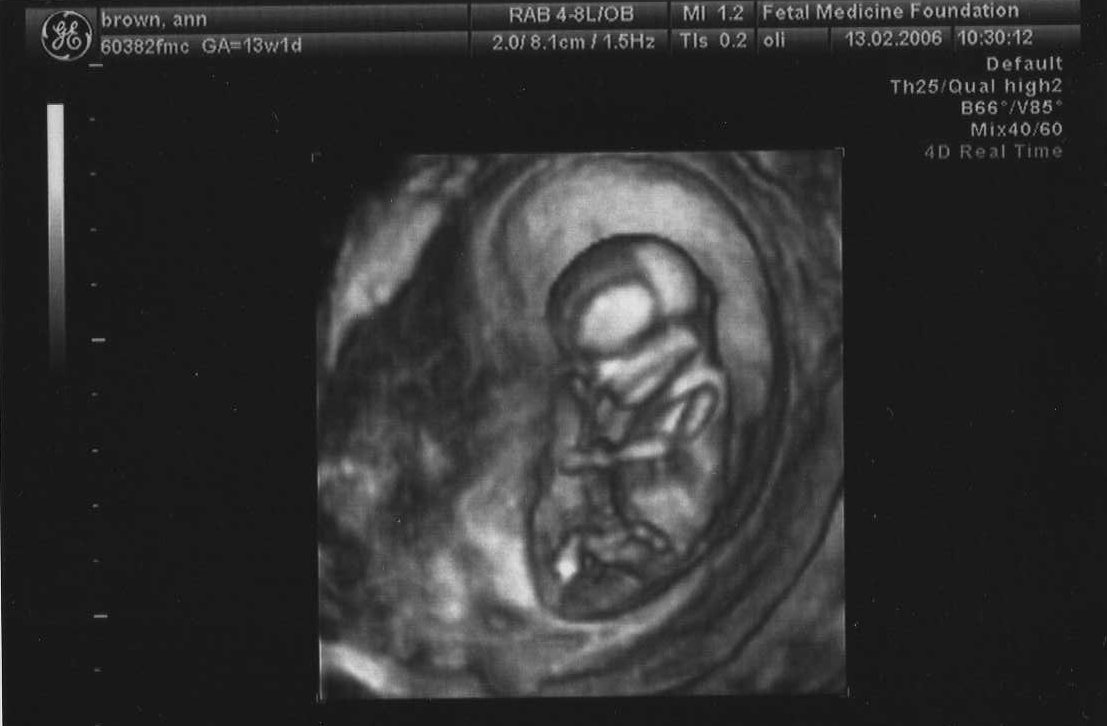

13th February 2006 (13 weeks) ... 3-D scan (6.9 cm head to rump)